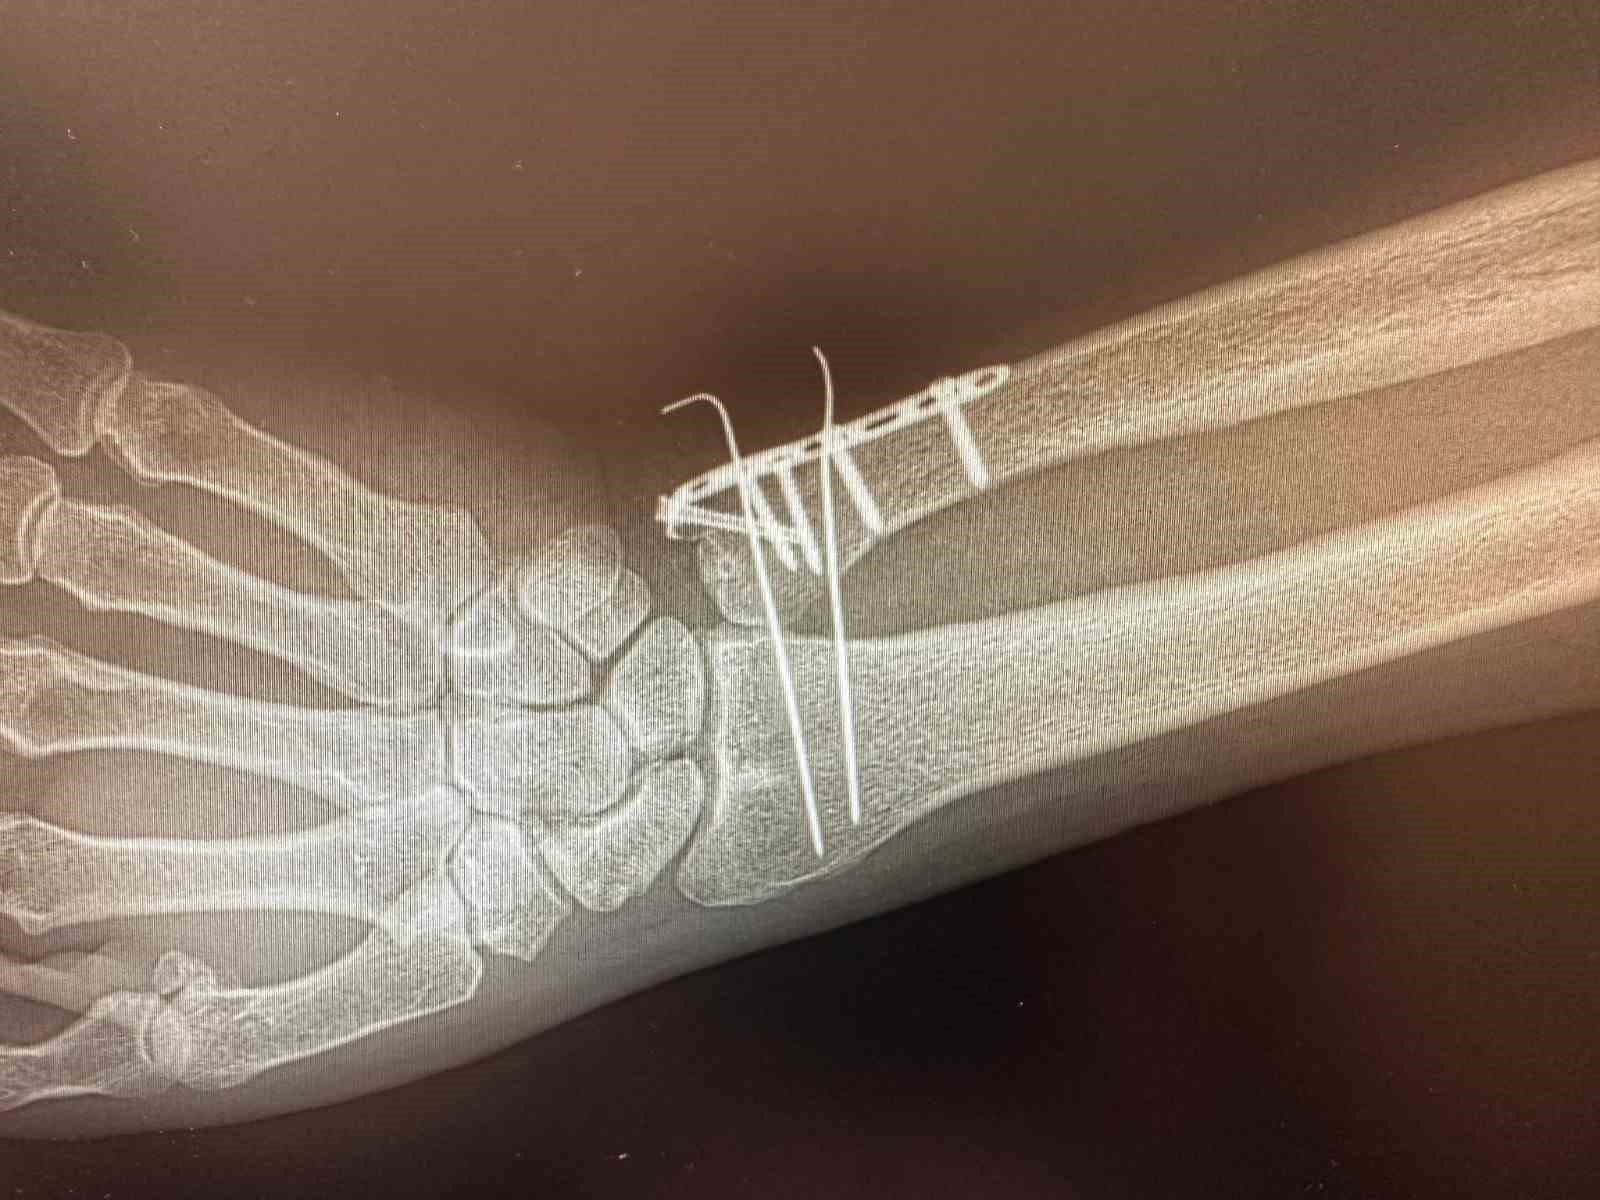

Karakoçan Devlet Hastanesi’nde ortopedi ameliyatlarının yapılabilmesi için C Kollu Skopi (C-arm) cihazı hastaneye tahsis edildi. Hastanede göreve başlayan Ortopedi Uzmanı Halil Sami Postallı tarafından, yeni cihazın kullanımıyla birlikte kemik ameliyatlarının yapılmaya başlandığı bildirildi.

C Kollu Skopinin ameliyathane ortamında hastanın iç yapısını anlık ve hareketli olarak görüntüleyen, X-ray tabanlı taşınabilir bir röntgen cihazı olduğu bildirildi. C şeklindeki yapısı sayesinde her açıdan görüntü alabilen cihazın özellikle ortopedi, travmatoloji, beyin cerrahisi, üroloji ve kardiyoloji işlemlerinde yüksek çözünürlüklü görüntü sağlayarak müdahalelerin daha güvenli ve hızlı yapılmasına imkan tanıdığını aktarıldı.

Cihazın özellikle kırıkların düzeltilmesi, vida ve plak uygulamaları, kalça ve diz protez ameliyatları gibi ortopedi ve travmatoloji işlemlerinde etkin şekilde kullanılacağı ifade edildi.